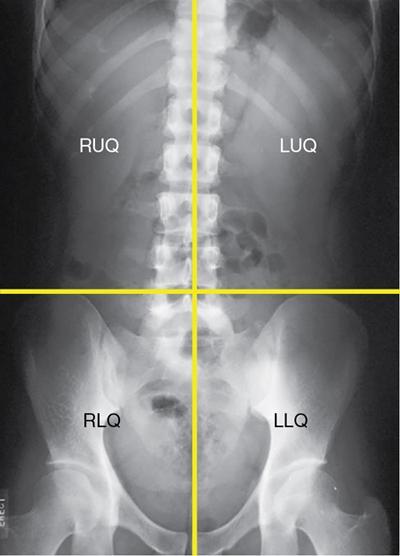

UNDERSTANDING THE ADULT ABDOMINAL RADIOGRAPH: TECHNIQUES AND INTERPRETATION Tanvi Modi Radiography of the abdomen is a common practice for the evaluation of abdominal organs. The anatomy and pathology of digestive, hepatobiliary and genitourinary systems can be assessed using radiographs, either as a stand-alone practice or as a primary imaging modality followed by contrast studies, ultrasound or cross-sectional imaging. In addition, abnormalities of the musculoskeletal or integumentary system can also be deduced on the basis of abdominal radiographs. This chapter intends to give an overview on the techniques and positioning in abdominal radiography as well as interpretation of normal and abnormal features. While superior imaging modalities such as ultrasound, computed tomography (CT), magnetic resonance imaging, capsule endoscopy and the likes have taken over abdominal imaging by and large, radiography still holds a pivotal role in certain situations and conditions, such as: The standard abdominal radiograph is taken in supine position and anteroposterior projection. This is also popularly known as the KUB (kidneys-ureters-bladder) radiograph. Previously, supine as well as erect radiographs were performed in all patients; however, this is not commonly done due to high-radiation dose. For all indications of abdominal radiography, including acute abdomen, supine radiographs are sufficient in terms of radiographic diagnosis, with the exception of perforation for which an erect chest or lateral decubitus radiograph can be performed if there is clinical suspicion. Patient should lie supine on the imaging table with median sagittal plane at right angles to the table and coincident with the midline of the table (Fig. 7.1.1.1). The body is divided into equal right and left halves by the median sagittal which passes through the sagittal suture of the skull. Pelvis should be adjusted so that the anterior superior iliac spines are equidistant from the table top. Gonadal shields, in the case of male patients, should be placed with the upper edge of the shield at the level of pubic symphysis. Although rarely used for female patients, these should be positioned between the anterior superior iliac spines and the pubic symphysis. The centre point of the image receptor should be approximately located at a point 1 cm below the line joining the iliac crests. The X-ray beam should be in a vertical direction, perpendicular to the table top and image receptor at the centre point. Collimation should be such that the soft tissue and subcutaneous region along lateral aspects of the abdominal cavity should be covered within the image. Also, the superior extent involving diaphragm and inferior extent involving the inferior pubic rami is important to look for any lower chest pathologies or any inguinal hernia. 35 × 43 cm (14 × 17 inches) in portrait orientation. On an average, abdominal radiograph exposes a patient to a dose of approximately 1.5 mSv, which is equivalent to 75 chest radiographs or 1/6th dose of a standard CT of the abdomen. The entrance skin dose is approximated to be 4 mGy. At such an effective dose, the additional lifetime risk of fatal cancer is 1 in 30,000. The exposure time is kept short. Patient is asked to exhale completely and hold their breath, with exposure taken at this point of full expiration to ensure imaging of abdominal organs in their natural positions. Modifications of this technique can be made depending on patient habitus and clinical condition. Kilovoltage peak (kVp) should be set to allow adequate visualization of abdominal soft tissue structures as well as semiopaque renal and biliary calculi. Average kVp is set at 70–85 kV. 102 cm (40 inches) Grids are commonly used to reduce scatter radiation. Placement of side marker on the image receptor at the time of radiographic exposure is essential. Bowel pattern depiction should be such that there is minimal lack of sharpness. Standard guidelines for abdominal radiography dictate that the radiograph should extend from the diaphragm up to the level of inferior pubic rami and must include the lateral abdominal wall musculature. The abdomen is divided into four quadrants on the basis of two perpendicular lines (Fig. 7.1.1.7). The vertical line passes through the mid sagittal plane and crosses the umbilicus and symphysis pubis. The horizontal line is a transverse line across the umbilicus at 90 degrees to the vertical line and is situated at the level of L4–L5 intervertebral disc. The quadrants are as follows: Another division system is dividing the abdominopelvic cavity into nine regions using two vertical and two horizontal planes (Fig. 7.1.1.8). The vertical planes, also known as the right and left lateral planes, are parallel to the midsagittal plane between midline and anterosuperior iliac spines on either side. Of the two horizontal planes, the upper transpyloric plane is at the level of lower border of L1 and the lower transtubercular plane is at the level of L5. The nine regions are: On a standard radiograph, the exposure should be such that the stomach, bowel loops, outlines of liver, spleen, kidneys, psoas muscles should be well identified. Also, lumbar transverse processes should be seen. Arch of the pubic symphysis should be visible to evaluate bladder region. A well-centred film without rotation will demonstrate bilaterally symmetrical lower ribs, iliac wings, ischial spines and obturator foramina. Different structures seen on an abdominal radiograph can be classified into five basic densities: Identification of different structures depends on the relative degree of contrast between their densities. The demarcation is clearer in chest and is diminished in abdomen due to relative similar soft tissue density of various structures. On a normal radiograph, relatively large amounts of gas in stomach and colon with minimal small bowel gas can be seen. Further, colonic gas can vary from negligible to extensive, mimicking obstruction pattern; however, usually the gas is enough to delineate colonic haustral pattern. Faecal matter gives a mottled appearance to colonic gas. Short-air fluid levels on an erect radiograph may be seen even in normal cases. The normal appearance of small bowel loops on an abdominal radiograph follows the rule of threes: Stomach is seen in the left upper quadrant and is visualized when distended with air. It is commonly seen extending from T11 to L2 level. Common feature identifying the stomach is the fundal gas which is usually seen as an air fluid level within the gastric lumen. Small bowel loops are distributed to the centre of the abdominal cavity and large bowel loops are peripheral. Duodenum is predominantly situated in right upper quadrant. It extends to left upper quadrant in the region of duodenojejunal flexure. Jejunum occupies the left upper and lower quadrants and is easily identified due to the presence of thick, numerous, closely spaced valvulae conniventes (Fig. 7.1.1.9A). The ileum occupies both lower quadrants and extends into right upper quadrant. Ileum has few and less prominent valvulae as compared to jejunum (Fig. 7.1.1.9B). Ascending and descending colon are retroperitoneal and have relatively fixed positions along lateral aspect of the abdominal cavity on either side. Transverse and sigmoid colon, on the other hand, may have a variable position due to their mobility along mesocolon and redundant pattern. These can be identified with confidence on account of haustrations and faecal matter (Fig. 7.1.1.10). Haustrations are usually well seen in ascending and transverse colon and poorly delineated beyond splenic flexure. Caecum is in the right lower quadrant, though it may be mobile or pulled up. Rectal gas is usually seen in the midline at the level of pelvis and its presence rules out large bowel obstruction. All these positions may vary due to anatomical conditions such as malrotation or pathological conditions, for example volvulus. Liver, spleen and renal outlines cannot be completely traced with precision due to the overlap by bowel loops. On a frontal projection, the liver appears as a triangular structure occupying right and left hypochondrium and epigastric region. Occasionally, the right lobe may be seen extending lower than the right renal shadow. This is a normal variant known as Reidel’s lobe. Gall bladder is situated in the posterior and inferior region of the liver and any pathology of the gall bladder should be looked for in this region. On a lateral radiograph, the gall bladder is anterior to the midcoronal plane. This helps in distinguishing gall bladder calculi from renal calculi, which will be more posteriorly situated. Spleen is seen in left upper quadrant/left hypochondrium, flushed to left lower ribs and left hemidiaphragm. Pancreas is present in the epigastric region (right and left upper quadrants) and is usually not identified in the absence of a pathology. The kidneys are bean-shaped retroperitoneal organs which are seen on either side of the vertebral column and lateral to psoas muscles. Due to the presence of liver on the right side, this kidney is slightly lower in position as compared to its contralateral counterpart. The visualization of kidneys on radiographs is facilitated by the surrounding fatty capsule. Kidneys lie between T11–12 and L2 level, with left kidney 1 cm higher than the right. Psoas muscle shadow can be normally seen along lateral aspect of lumbar spine bilaterally and is mildly concave (Fig. 7.1.1.11). Abdominal wall muscles are not routinely assessed on radiography; however, inclusion of lateral abdominal wall (muscles as well as subcutaneous plane) is a must while performing radiography. The flank stripe or the properitoneal fat stripe is a fat density linear concavity seen along lateral abdominal wall (Fig. 7.1.1.11). It is bound by the paracolic gutters and air-filled ascending and descending colon. All the solid organs in the abdomen are identified due to the fat density outlining them. Distortion of these fat lines helps in identifying organomegaly or focal mass lesions. The dome of urinary bladder is outlined by fat, which aids in differentiating its density from other soft tissue structures of the pelvis. Not all calcifications seen on abdominal radiograph are abnormal. Some may depict age-related changes such as vascular calcifications involving abdominal aorta, pelvic vessels, splenic artery in the region of left upper quadrant. Within the pelvis, phleboliths may be seen and mistaken for urinary calculi. Assessment of lumbosacral spine, iliac bones and femoral heads can be made on the basis of plain radiography. Degenerative changes may be commonly seen. Lower ribs can also be evaluated for pathologies. Dilated small bowel loops with rounded soft tissue density in midline over umbilical region suggests obstruction secondary to umbilical hernia. Pneumoperitoneum must be looked for in all cases of acute abdomen. While erect chest and left lateral decubitus radiographs can detect even 1 mL of free air, there are multiple signs on supine radiograph to suggest this diagnosis, for example Rigler’s sign, falciform ligament sign, football sign (Figs. 7.1.1.24 and 7.1.1.25). Retroperitoneal perforation may demonstrate air outlining psoas muscles and retroperitoneal organs. Small amount of free air may persist in the abdominal cavity up to 3 weeks after surgery, although it usually resolves within a week. Clinical history is important in such cases. Air foci within the bowel wall may represent bowel ischaemia/strangulation. Linear gas patterns in right hypochondrium may be due to two causes, that is pneumobilia and pneumoporta. The former can be seen normally postbiliary surgery, sphincterotomy, ERCP or in the case of abnormal fistulous communication between bowel and biliary tree (Fig. 7.1.1.26A). Pneumoporta (Fig. 7.1.1.26B) is a red flag and warrants further investigation to look for conditions such as mesenteric ischaemia and toxic megacolon. Pneumobilia is more centrally located whereas air shadows in pneumoporta are seen reaching up to periphery of liver. Air foci over renal shadows (Fig. 7.1.1.27), gall bladder or pancreas, in the absence of recent procedural history, suggest fulminant infection and mandate urgent intervention. Central midline calcific foci between T9 and T12 vertebrae can be attributed to calcific pancreatitis (Fig. 7.1.1.28). In the left upper quadrant, areas of calcification seen involving a shrunken spleen may be seen in autosplenectomy. In right upper quadrant, calcified gall stones may be seen. These tend to be small, multiple, uniformly circumscribed and ring-like in appearance with central translucency (Fig. 7.1.1.29A). Mercedes Benz sign, a triradiate pattern of gas lucency, is associated with gallstones. In contrast, renal calculi are more commonly solitary, irregular, of homogenous density, conform to renal calyceal or pelvic outline (Fig. 7.1.1.29B) and are sometimes of staghorn configuration. On lateral view, the gall stones are more anteriorly located as compared to renal calculi, which may be partly superimposed on lumbar vertebrae. Ureteric calculi tend to overlap bony structures such as lumbar transverse processes (Fig. 7.1.1.29B) or sacroiliac joints. Extensive or patchy, curvilinear calcification of gall bladder wall is known as porcelain gall bladder which is often associated with malignant transformation. Calcification involving adrenal glands may be secondary to infection or haematoma, or a congenital condition known as Wolman’s disease where there is bilateral involvement. Discontinuous discrete midline tram track calcification in the abdomen may indicate atherosclerotic changes in abdominal aorta and branch vessels. However, when the calcification is in a globular pattern and seen below the level of L2 vertebra, aortic aneurysm should be suspected (Fig. 7.1.1.30). Appendicoliths, though not commonly seen, may sometimes be detected in right iliac region. Pelvic calcifications: vesical calculi, distal ureteric or vesicoureteric junction calculi, calcified fibroids, ovarian dermoid with tooth-like calcifications (Fig. 7.1.1.31) may be the cause of abdominal pain and should be diligently looked for. Vesical calculi are usually more large and central in location whereas calcification due to fibroids may be more lateral. Schistosomiasis is another cause of bladder wall calcification, as is calcification of bladder tumours. Phleboliths tend to be bilaterally symmetrical, with a lucent centre unlike ureteric calculi. While it is believed that phleboliths are located below the level of ischial spines and ureteric calculi above, this is not always true and should be confirmed with CT. Fluid may collect adjacent to properitoneal fat line, forming a linear soft tissue density separating the fat line from the ascending or descending colon. Hellmer’s sign demonstrates medial displacement of lateral edge of liver (hepatic angle), due to fluid collection or ascites. Gross ascites may appear as generalized abdominal haziness or diffuse increased density of pelvis. Abscesses can involve any solid organ and in such cases may be difficult to demonstrate on plain radiography alone. Enlargement of organ or faint gas densities within can be suggestive of the same. In the case of peritoneal abscess, mottled density due to air, fluid and necrotic contents point towards this diagnosis, especially in right iliac fossa in association with appendicitis. Retroperitoneal abscess, similar to any retroperitoneal mass, may cause displacement of retroperitoneal structures (Fig. 7.1.1.32). Subdiaphragmatic abscesses may show concomitant ipsilateral pleural effusion (Fig. 7.1.1.33). These should be differentiated from Chilaiditi syndrome. Fluid and soft tissue lesions present with the same density on radiographs. While it is difficult to characterize the lesion and organ of origin, clues for the same can be provided by organomegaly (Fig. 7.1.1.34), distortion of fat surrounding solid organs, displacement of bowel loops or solid organs. For example, a retroperitoneal lesion may cause anterior or inferior displacement of kidney, a pelvic mass may cause upward displacement of small bowel loops. Different densities such as fat or calcification may help in identifying organ of origin (e.g. fat and tooth densities seen in ovarian dermoid). Convexity of margins of psoas muscle on an abdominal radiograph can be due to haematoma, abscess or intramuscular tumour. Radiographs are performed for the initial diagnosis of foreign body in the abdomen including type, number of foreign bodies, location, size and shape (Fig. 7.1.1.35). Radiolucent foreign bodies such as wood, plastic, chicken bones will not be easily identified on radiography. Low kVp (65–70 kVp) can increase contrast and help identify these objects. In addition to an abdominal radiograph, chest radiography is also performed to exclude aspiration or oesophageal location of foreign body. Ingested or introduced foreign bodies may cause complications such as obstruction, perforation, fistula formation and sepsis. Hence, once their presence is confirmed, follow up radiography must be performed until they are eliminated. One must look for fractures/dislocation injuries involving the vertebrae or pelvic bones, especially after history of trauma. Lucent expansile lesions or sclerotic bony deposits which represent neoplasms, absent pedicle sign in cases of metastasis, metabolic bony changes such as rugger jersey appearance, Paget’s disease, arthropathies such as ankylosing spondylitis with bamboo spine appearance and sacroiliitis (Fig. 7.1.1.36) are some of the conditions which may be diagnosed based on an abdominal radiograph. Overlap of bowel loops over iliac blades may lead to a misdiagnosis of lucent lesions and should be evaluated with caution. Basal pneumonia may be the cause of acute abdominal pain and should be looked for in abdominal radiography. Similarly, pleural effusion, pericardial effusion, calcified pleural plaques, achalasia, interstitial fibrosis are few other findings that can be seen in lower chest on an abdominal radiograph. Basilar atelectasis can give a deceptive appearance of pneumoperitoneum (Fig. 7.1.1.37). Surgical clips, commonly in right hypochondrium after cholecystectomy, drainage tubes, ventriculoperitoneal shunts, femoral line catheters, IVC filters, stents (vascular, renal, biliary) (Fig. 7.1.1.38), stoma bags, contraceptive devices are some structures that may be seen in an abdominal radiograph. Correct knowledge of patient history and normal locations of these structures prevents misdiagnosis. Certain artefacts may be projected upon the radiograph due to surface structures such as trouser buttons, body piercing, sequins over clothing and should not be considered as a pathology. Multiple skin surface nodules in cases of neurofibromatosis, soft tissue focal swellings, such as abscesses, lipomas, haematomas, desmoid tumours and malignant lesions may be incidentally seen on radiography. These can be further evaluated using ultrasound or CT. Subcutaneous emphysema is another finding that may be seen in lower abdominal wall secondary to retroperitoneal perforation or diffusely along abdominal wall in the case of bowel perforation (Fig. 7.1.1.39). Foreign bodies such as bullets and pins may be seen lodged in abdominal wall. A systematic approach to abdominal radiographs is important for accurate diagnosis as follows: Despite the development of newer techniques for imaging of the abdomen, plain radiography still holds an important place in the initial assessment of acute abdomen. Positive and negative findings on an abdominal radiograph can direct further investigation. Ideal positioning, recognition of normal appearances and keen scrutiny for pathologies is a sine qua non for radiologists reading a plain film of the abdomen. OESOPHAGOGRAM Padma V. Badhe, Vikram Reddy, Sultan Moinuddin Shaukatali, Zillani Alam, Ravi Varma, Abhishek Bairy, Dasari Ravikiran, Revati Tekwani, Soniya Patankar, Megha Nair, Gautham Shankar Oesophagogram is the process of obtaining radiological images and simultaneous motion recording to evaluate function and disorders of pharynx, oesophagus and proximal stomach. Oesophagogram is usually done primarily to evaluate dysphagia. Some of the common indications are oesophageal motility disorders, strictures, gastro-oesophageal reflux disease (GERD) and suspected masses. It can also be used to detect uncommon anomalies like vascular rings/slings and aberrant anatomy. It also helps to evaluate further in cases where there is inability to pass upper GI scope. Double-contrast oesophagogram is mainly indicated in early mucosal disease like erosion, polyp, infection and tumours. If a motility disorder is suspected, dynamic technique (e.g. videofluoroscopy) is used for dysphagia or aspirations in cases of stroke, neuromuscular disorders, post head and neck surgery or radiation. Barium oesophagogram is contraindicated in suspected cases of perforation and tracheoesophageal fistula, aspiration, rarely if there is hypersensitivity to barium suspensions. It is also contraindicated in suspected oesophageal perforation where a water-soluble contrast agent is more suitable. However, ionic water-soluble contrast agent is better avoided in cases of aspiration or fistula with airway. The contrast examination of the pharynx is dangerous in cases of acute epiglottitis and must be ruled out on plain radiograph. An 80% w/v barium suspension is used in full column views. However, 200%–250% w/v barium suspensions is usually required for mucosal relief films. The barium sulphate mixture is fed to the patient either by spoon, by glass, or through a drinking straw, depending on its consistency. In videofluoroscopy, the pharyngeal phase of swallowing is usually safer with barium pudding than with thick barium and safer with thick barium than with thin barium. However, if the major abnormality is poor pharyngeal contraction leading to stasis in the piriform sinus (and epiglottic tilt is normal), a thin liquid is safer. Epiglottic motility is better assessed with thin barium because thick barium often obscures the epiglottic tip. Fluoroscopic equipment capable of cine fluoroscopy and capability for rapid sequence spot images (high frame rate) is needed for this examination, Barium suspension, straw, glass, Lead apron and radiation protective equipment. The patients are instructed to fast after midnight before the day of the examination. The pharynx should be made as dry as possible during the examination as high-density barium adheres to dry pharyngeal mucosa. Activities like smoking, chewing gum and lozenges must be abstained before the procedure as they impair barium coating by increasing the salivary secretion. Regular oral medications must be taken with sips of water; however, insulin must be skipped on the morning of examination. The major principles of a good oesophagogram includes mucosal coating, distension and projection. A routine oesophagogram consists of screening of the oral, pharyngeal and oesophageal phases of swallowing, single and double-contrast examination of pharynx, single contrast, double-contrast and mucosal relief views of the oesophagus. In cases of dysphagia, the examination is tailored depending on whether the symptoms are either pharyngeal or oesophageal and initial fluoroscopic findings. If patients’ symptoms are suggestive of oral or pharyngeal disorder then pharynx is evaluated first. Similarly, if patient is suspected to have thoracic oesophageal disease then, double-contrast examination of the oesophagus is performed before the pharyngeal evaluation. During an oesophagogram the positioning of the patient varies according to the type of examination (Table 7.1.2.1).